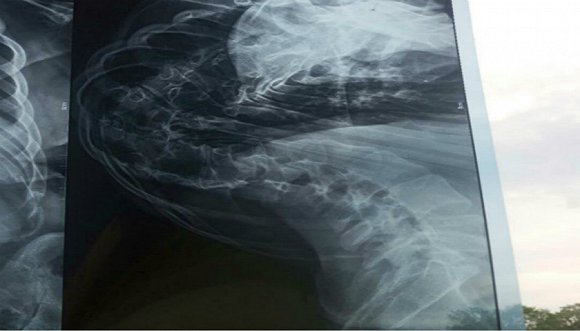

从侧面拍摄的傅月的脊柱CT图像。图片来源:受访者提供